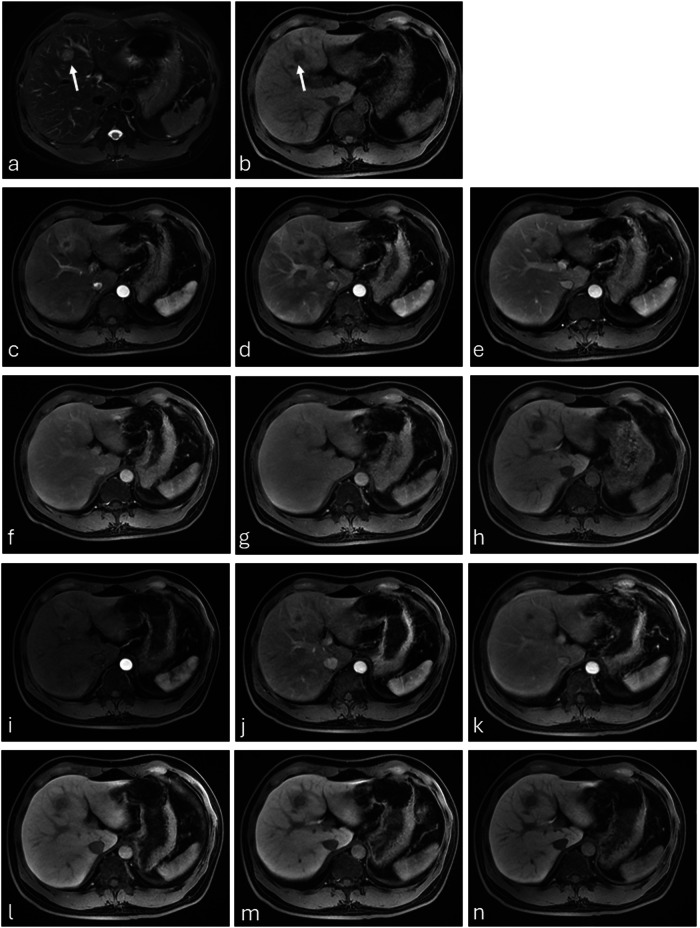

Abstract Image